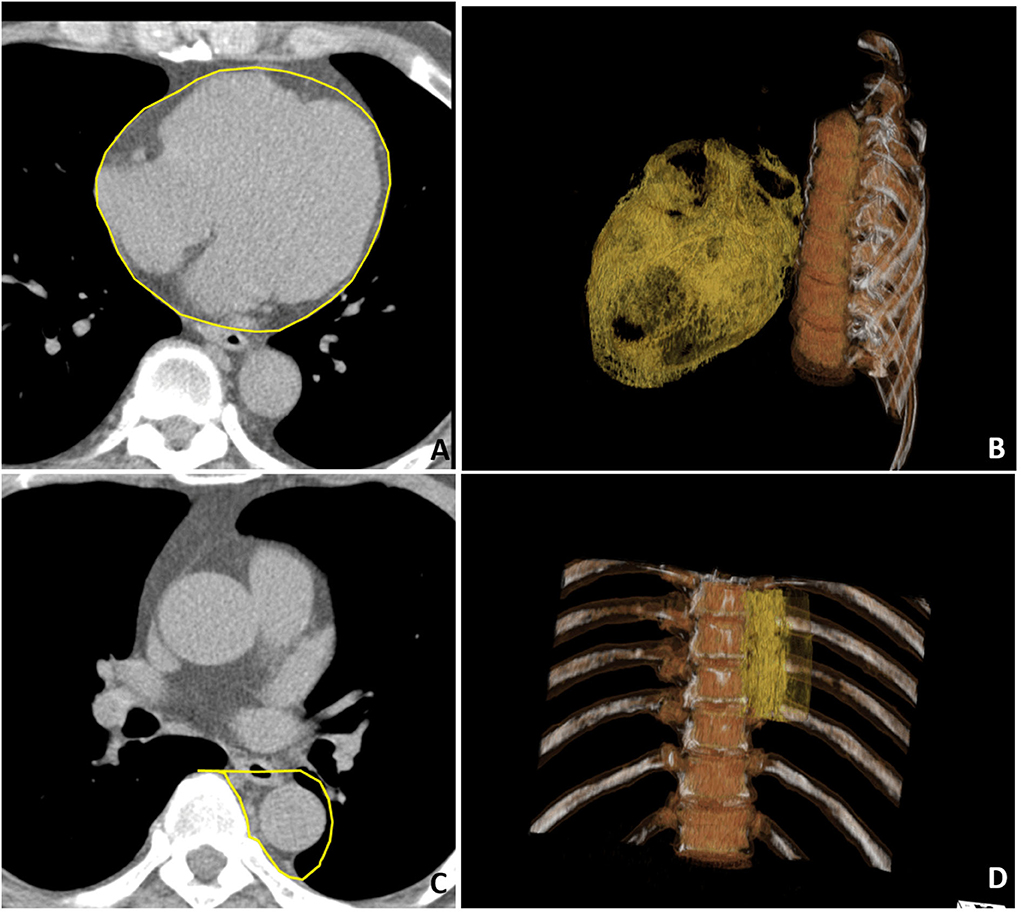

Cardiac computed tomography was performed by using a 16-slice MDCT scanner (Sensation 16, Siemens Medical Solutions, Forchheim, Germany) as demonstrated in a previous study (5). In brief, images were acquired from above the level of tracheal bifurcation to below the base of the heart using prospectively ECG triggering with the center of the acquisition at 70% of the R-R interval during one breath-hold period. From the raw data, the images were reconstructed with a standard kernel in 3 mm thick axial, non-overlapping slices, and a 25 cm field of view. Visceral adipose tissue of EAT and PAF was quantified by MDCT using a dedicated workstation (Aquarius 3D Workstation, TeraRecon, San Mateo, CA, USA). We traced the region of interest manually and defined fat tissue as pixels within a window of −195 to −45 Hounsfield unit (HU) and a window center of −120 HU. EAT was defined as any adipose tissue located within the pericardial sac (Figures 1A,B). Thoracic PAF was defined as the adipose tissue surrounding the thoracic aorta, which extended 67.5 mm from the level of the bifurcation of pulmonary arteries (Figures 1C,D) with cranial-caudal coverage of the thoracic aorta. Detailed methods conducted in our laboratory for similar measures have been published elsewhere (5, 17, 18).

Figure 1